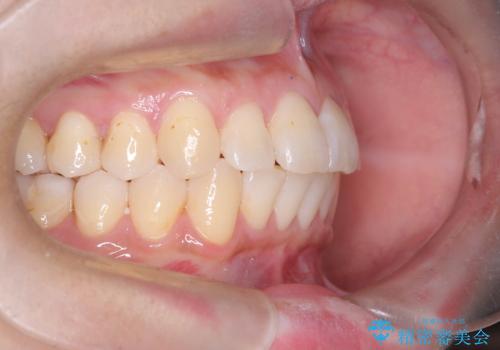

非抜歯で整える前歯の矯正

- 患者様は、前歯の重なり(叢生)が気になるとのことでご来院されました。診断の結果、奥歯を後方に移動することで前歯にスペースを確保し、非抜歯で歯列を整える方針としました。治療には審美性の高いホワイトワイヤーを使用し、奥歯の遠心移動にはリンガルアーチを装着しました。治療期間は約2年を予定し、月に一度の調整を通じて歯の動きを細かく管理しました。

非抜歯矯正は、歯を抜かずに自然な歯列を作るため、歯列全体のバランスを考慮する必要があります。本症例では、リンガルアーチによる奥歯の遠心移動を用いましたが、初期段階で軽い違和感を覚える方もいらっしゃいます。そのため、装置装着後のケアや食生活について詳しく説明を行い、患者様にも協力いただきました。また、審美ワイヤーを使用することで、日常生活での見た目のストレスを軽減し、治療を快適に進めることができました。